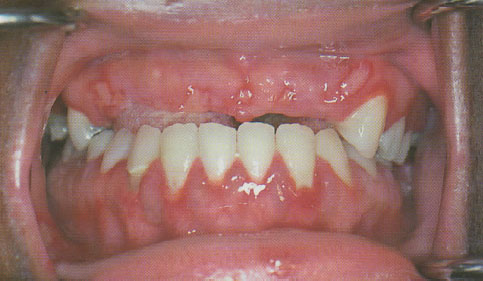

Em pacientes sintomáticos, a infecção primária produz um padrão de ulceração intra-oral típico conhecido como gengivoestomatite herpética primária. Os sintomas iniciais clássicos são febre e linfadenopatia, seguidos, durante alguns dias, por um envolvimento da mucosa gengival e oral. Em todos os pacientes com sintomas, a gengiva apresenta uma intensa alteração eritematosa dolorosa, exibindo, com frequência, cortes ou ulcerações na gengiva marginal livre. Pouco tempo depois, há o desenvolvimento de frágeis vesículas multifocais sobre toda a superfície mucosa intra-oral; as quais ulceram rapidamente. As ulcerações individuais geralmente têm poucos milímetros de diâmetro, mas formam um conglomerado e podem coalescer; além disso, podem-se assemelhar à estomatite aftosa menor, mas o envolvimento gengival intenso, febre e a presença de ulcerações na mucosa inserida direcionam a um diagnóstico diferencial.

Ulcerações multifocais presentes na mucosa livre e inserida. Observe na gengiva intensos eritemas sem placa.